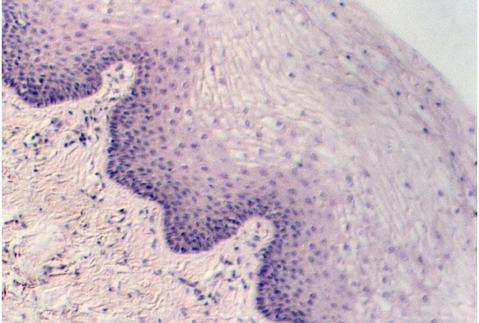

Slide 86 shows a uterus in the proliferative phase. The endometrium is illustrated in the photograph below. Note that the cells are low columnar to high columnar. The glands are relatively straight with a narrow lumina. Outside the glands is the highly cellular lamina propria. The following photos illustrate the proliferative phase with higher magnifications.

After ovulation, the uterine lining becomes more tortuous. The lining is now under the control of progesterone. This steroid hormone stimulates the lining to secrete material that may help nourish both sperm and a potential pregnancy. The glands expand and the lumina are wide and contain products of secretion. The glandular epithelium may be characterized by a droplet of secretory material under the nucleus (near the base) about 2 days after ovulation (day 16). Then, the secretory products move more towards the lumen. Slide 87 shows the Secretory phase of the uterine lining. Note the sections showing coiled or tortuous glands and the dense lamina propria.